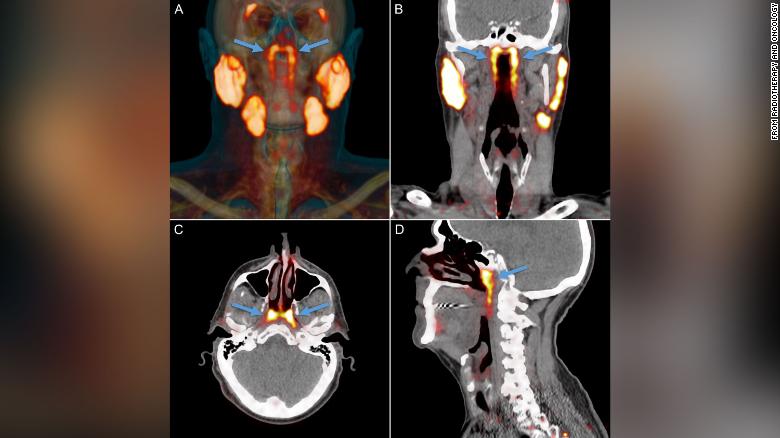

Según ha publicado la CNN, los investigadores encontraron por primera vez la parte del cuerpo, que proponen nombrar glándulas tubarias, durante una exploración diseñada para buscar crecimientos tumorales, ha señalado el autor principal del estudio, Matthijs H. Valstar, cirujano del departamento de oncología y cirugía de cabeza y cuello del Instituto del Cáncer de Países Bajos.

Asimismo, los científicos observaron escaneos de la cabeza y el cuello de otras 100 personas que estaban tratando por cáncer de próstata y diseccionaron dos cadáveres, uno masculino y otro femenino. En todos los análisis encontraron las glándulas, según se publicó en la revista Radiotherapy and Oncology.

Las glándulas no se pueden ver con métodos convencionales de imágenes médicas como ultrasonido, tomografías computarizadas o imágenes de resonancia magnética. El nuevo órgano solo se identificó cuando los médicos utilizaban un tipo de exploración nuevo y avanzado llamado PSMA PET/CT que se ha utilizado para detectar la propagación del cáncer de próstata.

PSMA PET es la abreviatura de la obtención de imágenes de antígeno de membrana específico de la próstata mediante tomografía por emisión de positrones. "Las personas tienen tres conjuntos de glándulas salivales grandes, pero no allí". Así dijo el autor del estudio Wouter Vogel, un oncólogo radioterapeuta del Instituto del Cáncer de los Países Bajos.